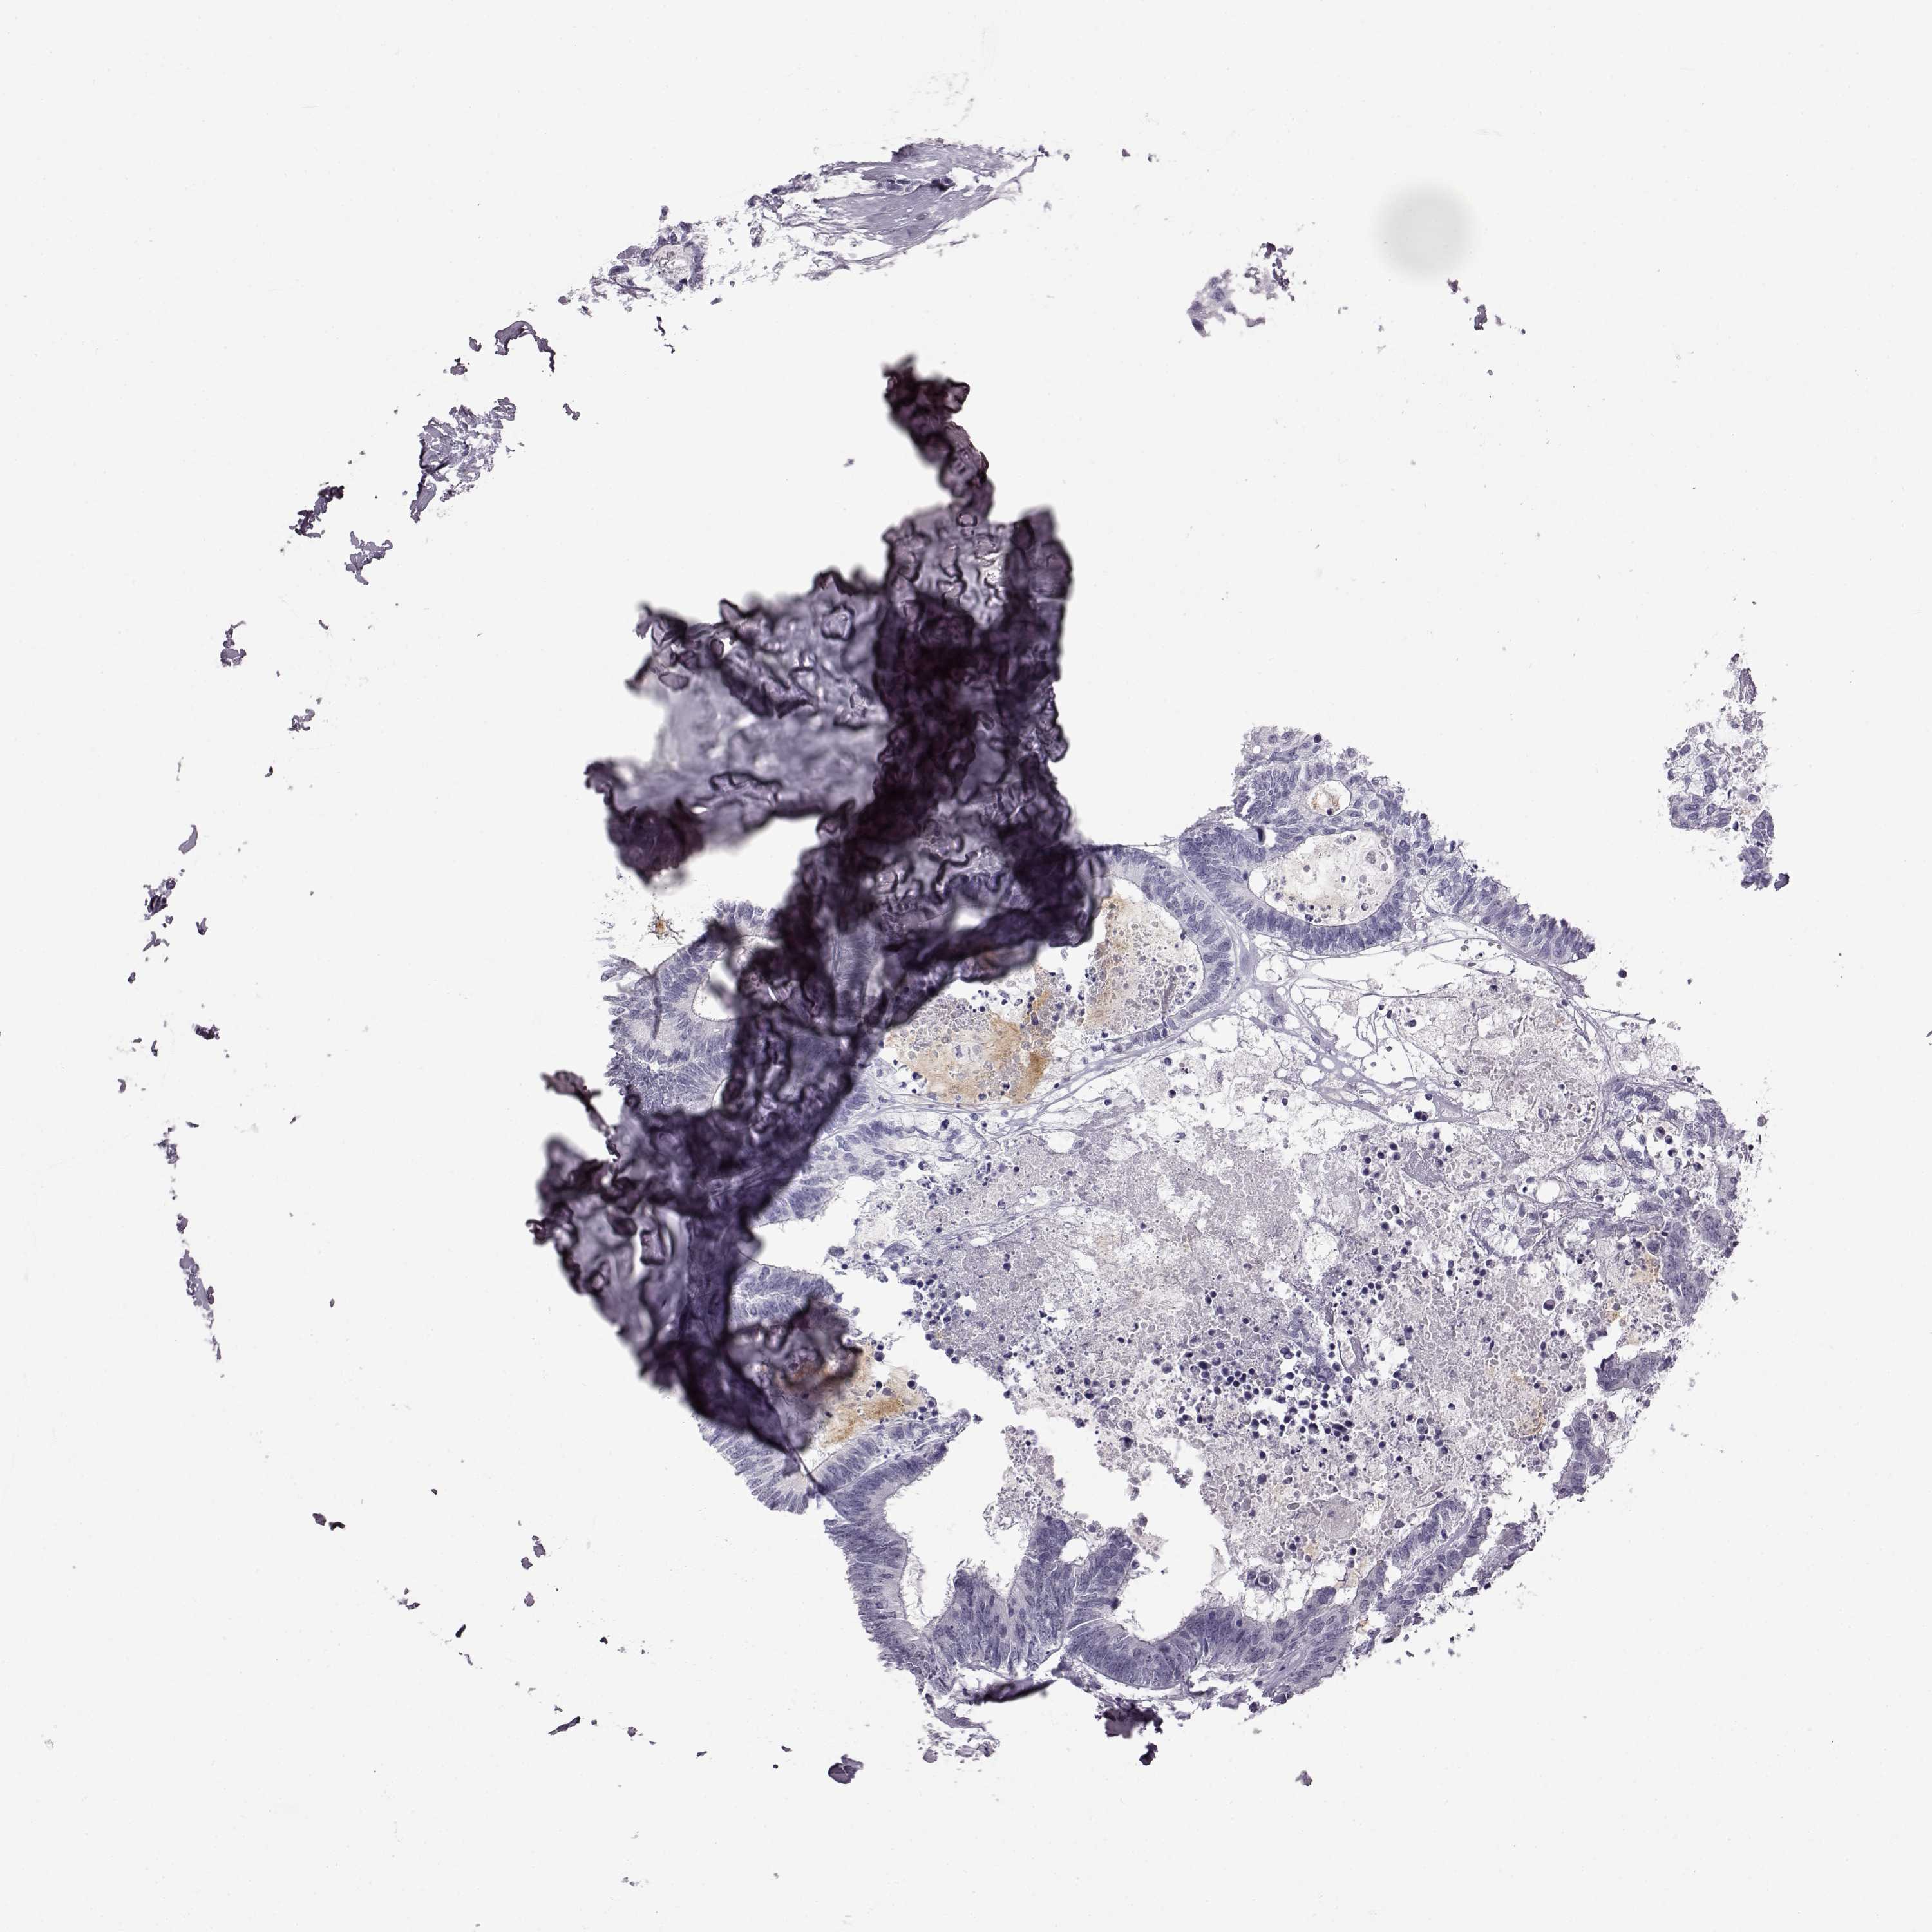

CANCER COLORECTAL CANCER Show tissue menu

COAD TCGA COAD VALIDATION READ TCGA READ VALIDATION PROTEIN COAD CPTAC PROTEIN EXPRESSION

Colorectal cancer

Colon adenocarcinoma